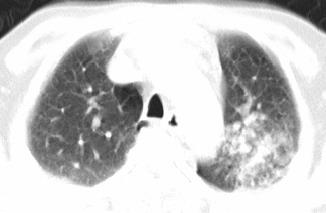

以下是引用xianxianzhongyi在2008-4-20 14:44:00的发言:[br]本人愚见:次病例短短两月的时间,呈现如此大面积实变,病变增长过于迅速,此其一。其二,病变在动脉早期既有明显强化。其三,左上叶后段及下叶背段多叶受累。其四,肺门及纵隔内未见明显肿大的淋巴结。估计层面较厚段支气管显示不清。 诊断:炎性实变可能性大。

以下是引用光影相伴在2008-4-20 14:39:00的发言:[br]支持:1)左侧中央型肺癌伴左肺上叶阻塞性肺炎。、[br] 2)双侧少量胸腔积液。